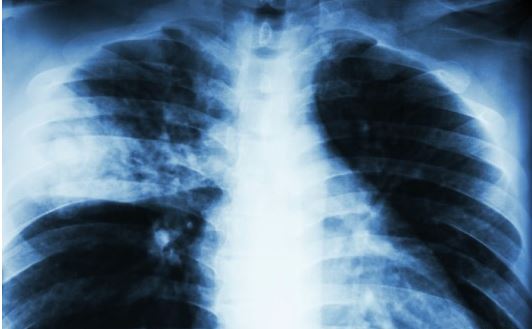

폐렴은 이 폐포에 세균감염으로 염증이 생긴 것을 말해요.

폐렴은 영유아부터 노인까지 다양한 연령에서 발병하는 질환이다. 요즘처럼 일교차가 큰 환절기나 추운 겨울에 많이 발생하는데, 초기에는 발열, 오한, 기침, 가래 등 감기와 증상이 비슷해 방치하기 쉽다. 하지만 적절한 치료를 받지 못하면 급속하게 증상이 나빠지고, 다양한 합병증을 일으켜 노년층이나 만성질환자는 심하면 사망에도 이를 수 있다.